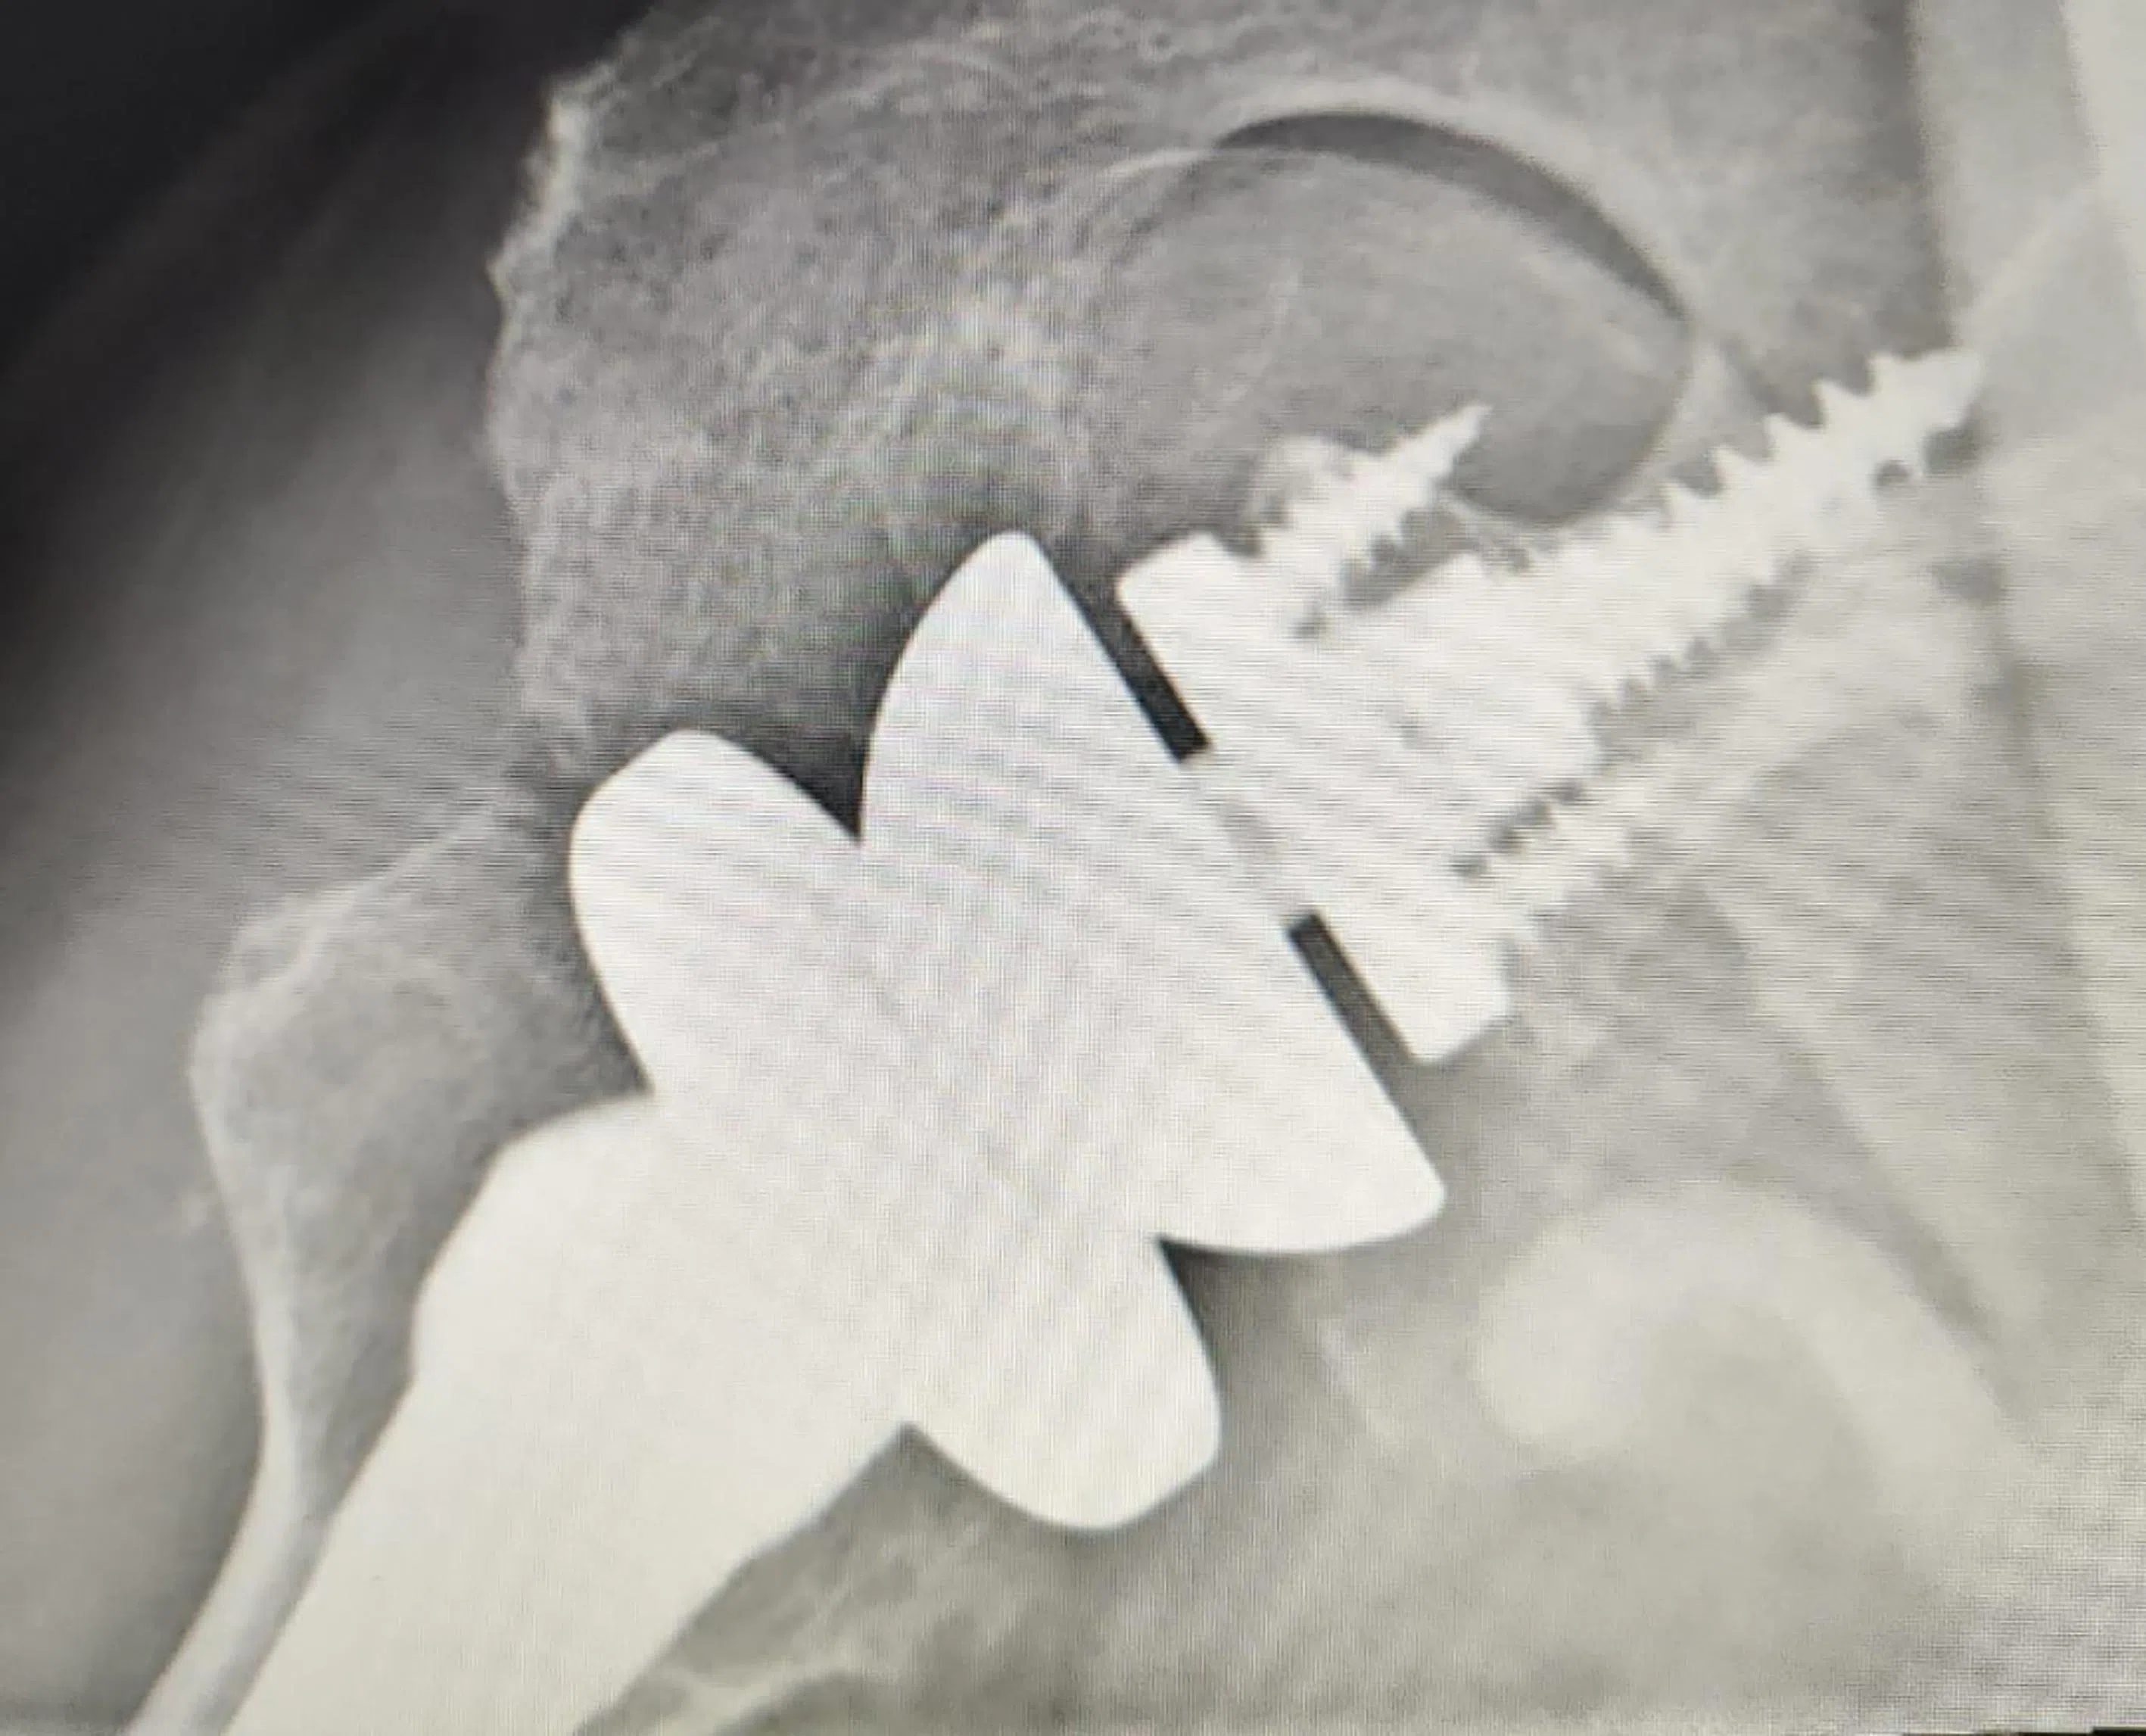

3. The virtual surgical planning of the humerus implant used in shoulder replacements results in higher accuracy, and reduces surgical time and complications.

Software tools are used for finite element analysis, and computational modelling is used to simulate biomechanical behaviour under various conditions. The different colours show varying levels of loading on the shoulder.